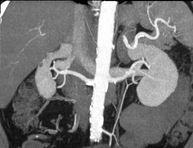

Prueba diagnóstica que consiste en obtener imágenes bi y tridimensionales del riñón y del sistema urinario de alta definición anatómica mediante el empleo de un equipo de TC (Tomografía Computarizada). Se realiza el estudio antes y después del empleo de contraste yodado en diferentes "fases renales" para una valoración funcional y anatómica (parénquima renal, uréteres, vejiga urinaria, arterias y venas renales, etc.), así como las estructuras adyacentes (vena cava inferior, aorta abdominal, hígado, bazo, etc.). Está especialmente indicado ante la sospecha de lesiones renales, en pacientes con sangre en orina o hematuria, etc. - TC Urológico

Prova diagnòstica no invasiva que consisteix en l'estudi de les artèries renals amb l'obtenció d'imatges d'alta definició anatòmica mitjançant l'ús d'un equip de TC (Tomografia Computaritzada) i contrast iodat. La qualitat de les imatges permet realitzar reconstruccions en 2D i 3D gràcies a estacions de treball especialitzades en l'estudi arterial. Aquesta prova està indicat en aquells pacients que pateixen HTA refractària al tractament, en pacients amb lesions renals que tenen un mapa vascular prequirúrgic, etc. - Angio TC d'aorta-ilíaca